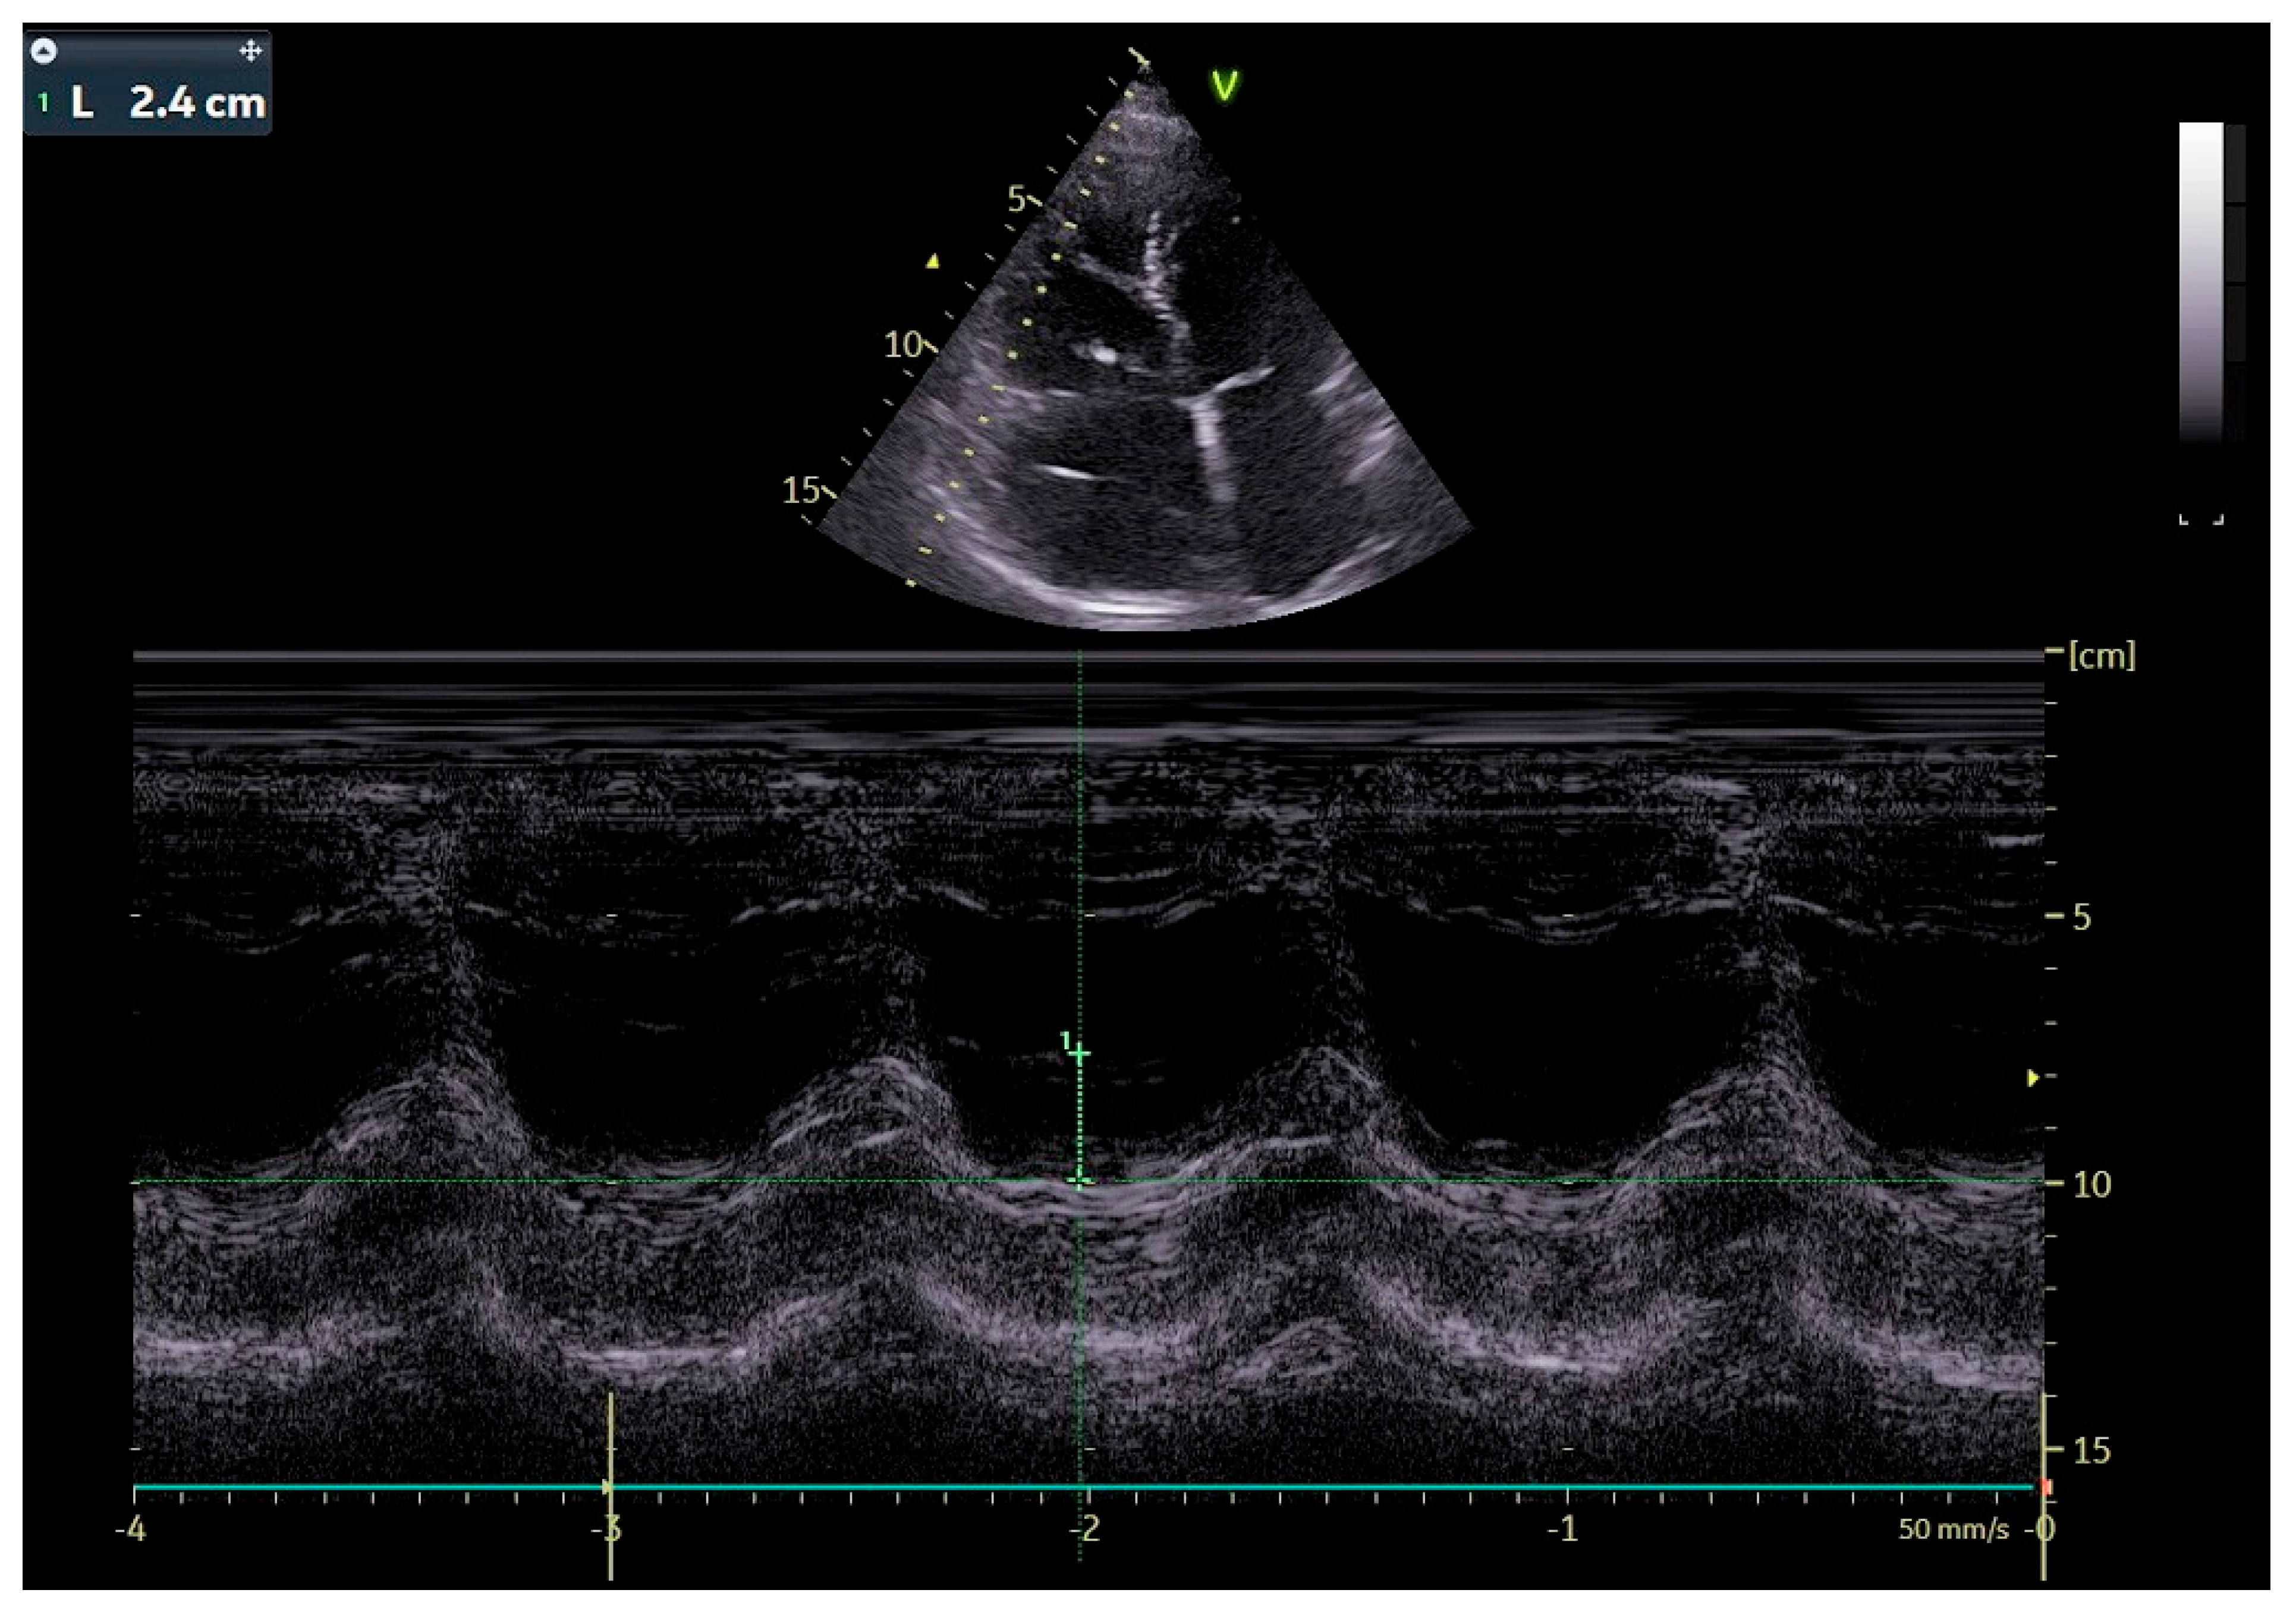

The patient was transferred to our hospital due to another exacerbation of HF. Echocardiography revealed severe tricuspid valve regurgitation (TR) (Figure 2). The tricuspid valve septal cusp was in a restricting position due to the two ventricular leads passing through the valve. The tricuspid valve leaflets had no coaptation. The right ventricle’s function was normal (Figure 3). After radiation therapy, increased scarring was found on the chest skin (Figure 4). One year ago, the patient underwent skin grafts due to healing wounds on her chest. The remaining right ventricle and atrium leads were transvenously removed. However, the procedure did not reduce tricuspid regurgitation (Figure 5).

Figure 3. Echocardiographic image, M-mode, evaluation of RV systolic function: tricuspid annular plane systolic excursion (TAPSE).